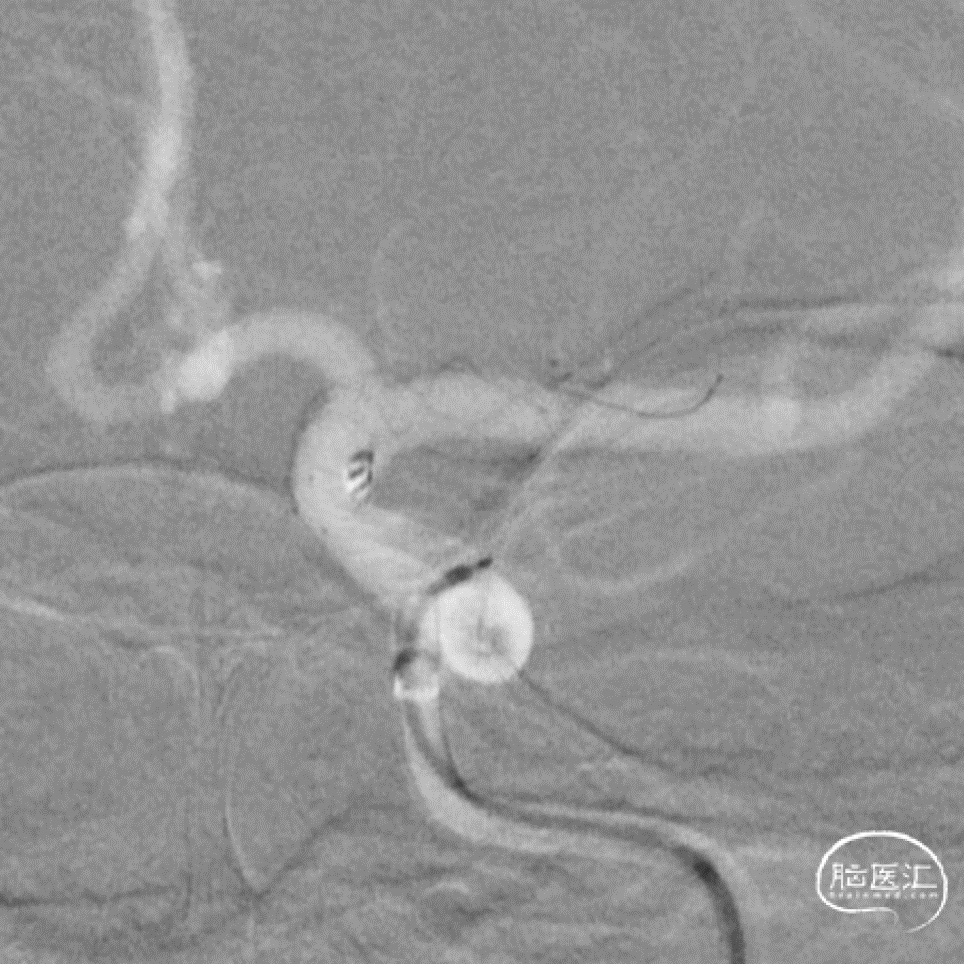

微导丝按摩

按摩后支架的形态

支架和弹簧圈重建的形态